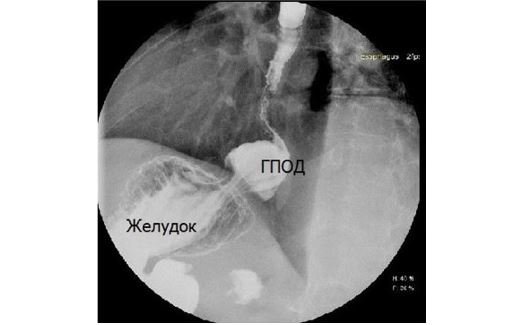

Лапароскопическая фундопликация – это операция преимущественного выбора при грыже пищеводного отверстия диафрагмы и гастроэзофагеальной рефлюксной болезни (ГЭРБ).

Операции по поводу ГПОД и ГЭРБ могут проводиться открытым методом (посредством проведения большого разреза) или лапароскопическим (малоинвазивным) методом, который проводится через несколько малых разрезов на передней брюшной стенке. У применяемого в нашей клинике лапароскопического метода есть несколько очевидных преимуществ по сравнению с открытым методом: эстетичность (очень маленькие рубцы после операции), меньший риск инфекционных осложнений, минимально выраженный дискомфорт в области ран, меньшее время госпитализации и более быстрый процесс реабилитации после операции.

Сама операция включает в себя низведение в брюшную полость до нормального уровня органов, находящихся в диафрагмальной грыже (желудок, брюшной отдел пищевода), выделение из рубцов и сращений стенки пищевода и желудка, иссечение грыжевого мешка, реконструкцию кардиального клапана, восстановление нормальных размеров пищеводного отверстия диафрагмы.

При реконструкции кардиального клапана мы используем методику, в наибольшей степени воссоздающую нормальные анатомические взаимоотношения и гарантирующую предотвращение рефлюкса желудочного содержимого в пищевод, - так называемую фундопликацию (fundus – дно желудка, plicatio – складывание) по методу Toupet-Nissen. Во время операции после бескровного выделения из рубцовых сращений и тканей грыжевого мешка стенки желудка, пищевода и мышц, образующих пищеводное отверстие диафрагмы, желудок и абдоминальный отдел пищевода низводятся в брюшную полость. Из передней и задней стенок дна желудка производится формирование манжеты, циркулярно охватывающей брюшной отдел пищевода и область кардии. При этом дополнительно накладываются швы, максимально высоко фиксирующие стенку желудка к пищеводу и воссоздающие острый угол Гиса. Таким образом создается антирефлюксная клапанная структура, выполняющая функцию нормальной кардии. В завершение операции наложением ряда швов проводится восстановление нормального диаметра пищеводного отверстия диафрагмы.